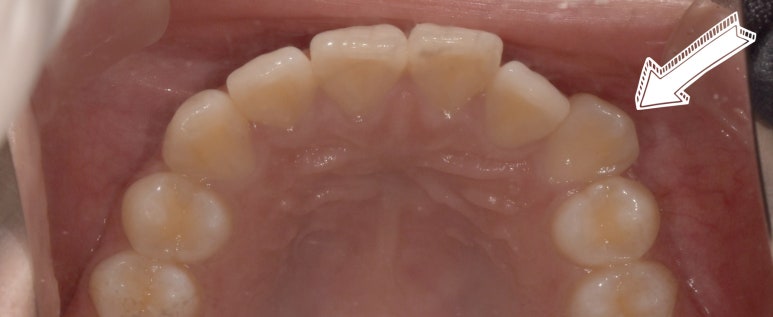

환자분은 다른 치아들은 비교적 가지런한 편인데 왼쪽 3번째 송곳니 (사진상 오른쪽)

#23 치아가 다소 뻐드러져있는 상태였습니다.

그래서 최대한 이 치아를 가지런하게 정돈하는 것을 목표로 치아 1개만 라미네이트 치료를 하기로 했고요.

사실 이렇게 다른 치아보다 앞으로 많이 튀어나온 치아들은

입술과 맞닿는 부분을 많이 깎아내야 다른 치아와 유사하게 맞출 수 있기 때문에 치아 삭제량이 많아질 수밖에 없습니다.